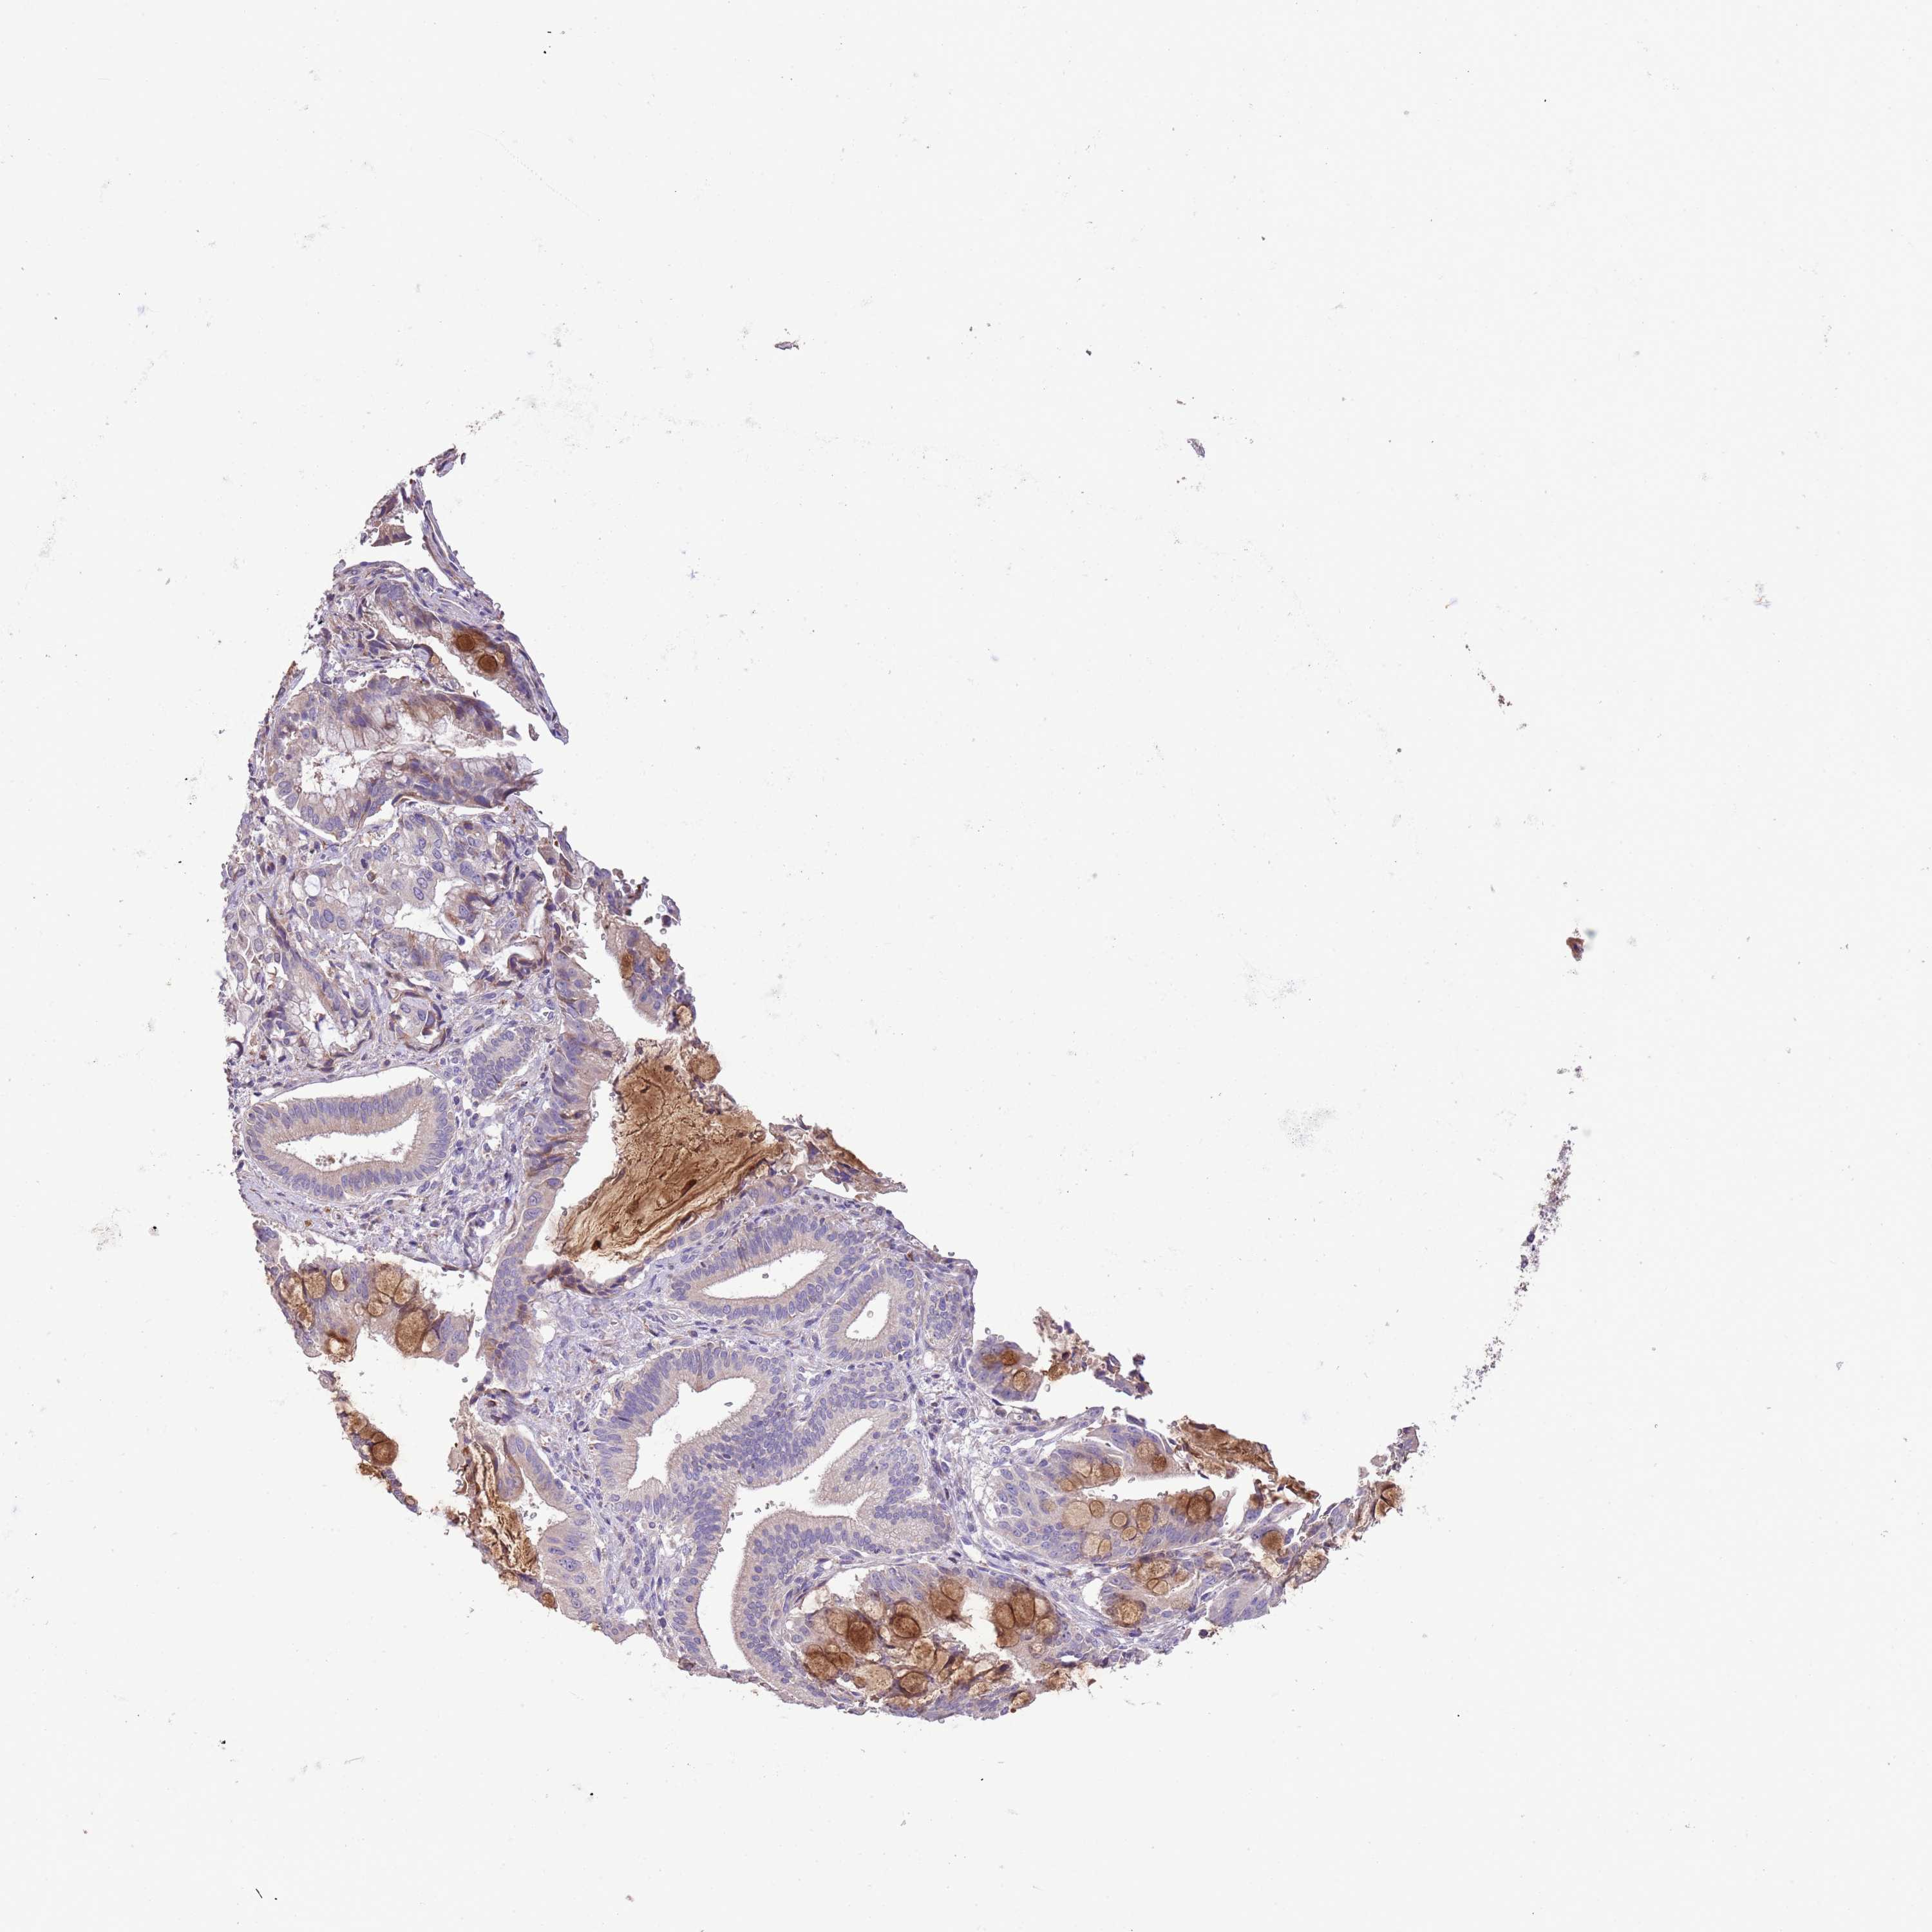

PANCREATIC CANCER - Protein expressioni

A mouse-over function shows sample information and annotation data. Click on an image to view it in a full screen mode. Samples can be filtered based on level of antibody staining by selecting one or several of the following categories: high, medium, low and not detected. The assay and annotation is described here.

Note that samples used for immunohistochemistry by the Human Protein Atlas do not correspond to samples in the TCGA dataset.

Antibody stainingi

Antibody staining in the annotated cell types in the current human tissue is reported as not detected, low, medium, or high, based on conventional immunohistochemistry profiling in selected tissues. This score is based on the combination of the staining intensity and fraction of stained cells.

Each image is clickable and will lead to virtual microscopy that enables deeper exploration of all samples and also displays staining intensity scores, fraction scores and subcellular localization as well as patient and tissue information for each sample.

Antibody HPA001174

Staining

High

Medium

Low

Not detected

Intensity

Strong

Moderate

Weak

Negative

Quantity

>75%

75%-25%

<25%

None

Location

Nuclear

Cytoplasmic/membranous

Cytoplasmic/membranous,nuclear

Adenocarcinoma, NOS